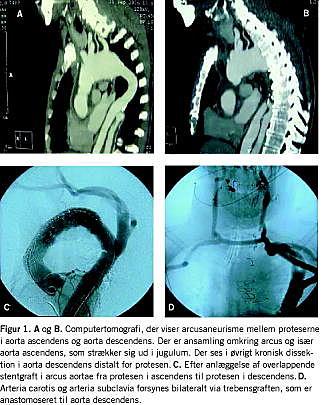

Den voldsomme pulsation i udfyldningen samt den hurtige udvikling, gjorde, at der var klinisk mistanke om et ekspansivt PA, og derfor afstod man fra punktur. Computertomografi viste en ansamling i jugulum, der kommunikerede retrosternalt med en tidligere konstateret ansamling omkring ascendens-rørprotesen (Figur 1 A+B). Ansamlingen omfattede som noget nyt også descendensprotesen, transøsofageal ekkokardiografi viste en tydelig lækage til ansamlingen ved overgangen mellem aorta descendens og arcus aorta i relation til rørproteseanastomosen. Endvidere blev der påvist et nydannet arcusaneurisme på 6 cm i diameter mellem de to proteser.

Dagen efter blev der anlagt overlappende stentgrafts fra ascendensprotesen i den aneurismatiske arcus aorta og ned over den proksimale anastomose af descendensprotesen (Figur 1 C+D ). Endvidere blev venstre a. vertebralis coilet. Højre a. vertebralis blev ligeret under operationen, og patienten blev således afhængig af en intakt circulus arteriosus.